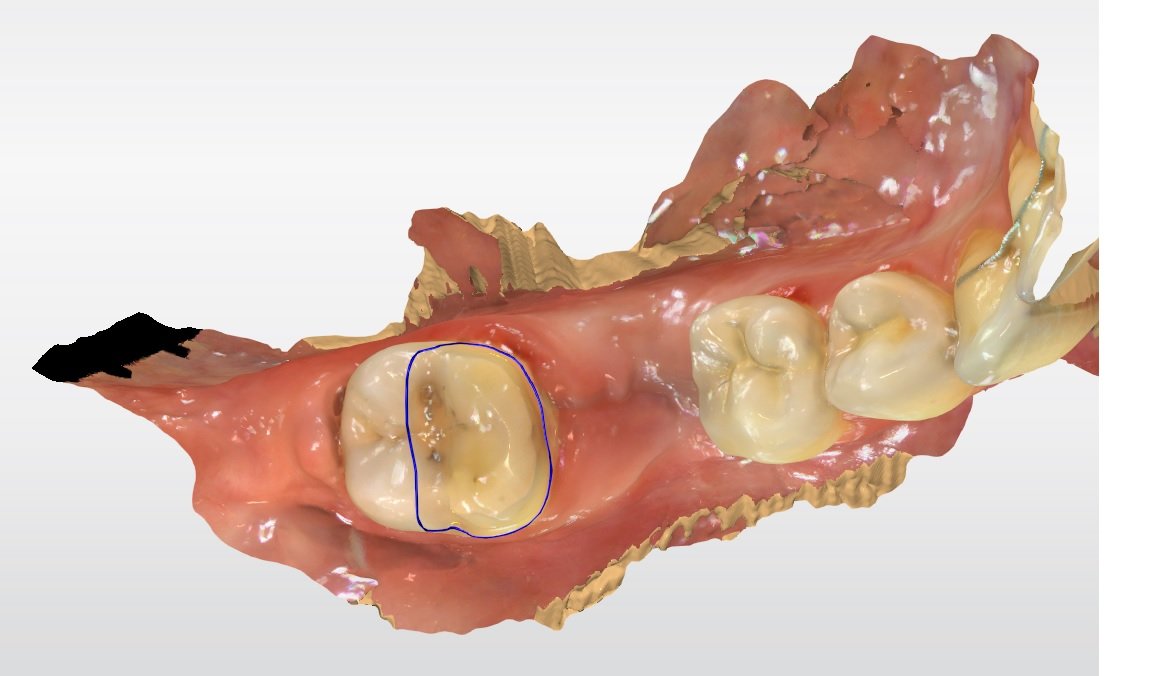

Relativement récents, les bridges collés cantilever postérieurs constituent une alternative fixe, fiable et véritablement minimalement invasive aux implants dans les secteurs postérieurs. Cette thérapeutique qui repose sur des indications bien précises est parfois débattue avec passion sur les réseaux sociaux ou dans les congrès scientifiques. Cependant des études cliniques existent, tout comme des recommandations validées dans des journaux internationaux. Leur succès repose sur des préparations et des principes biomécaniques rigoureux, pourtant simples à intégrer au quotidien. Cette intervention propose un guide clair et opérationnel incluant indications, étapes clés, protocoles d’adhésion et réglages occlusaux pour les mettre en œuvre avec confiance et reproductibilité.